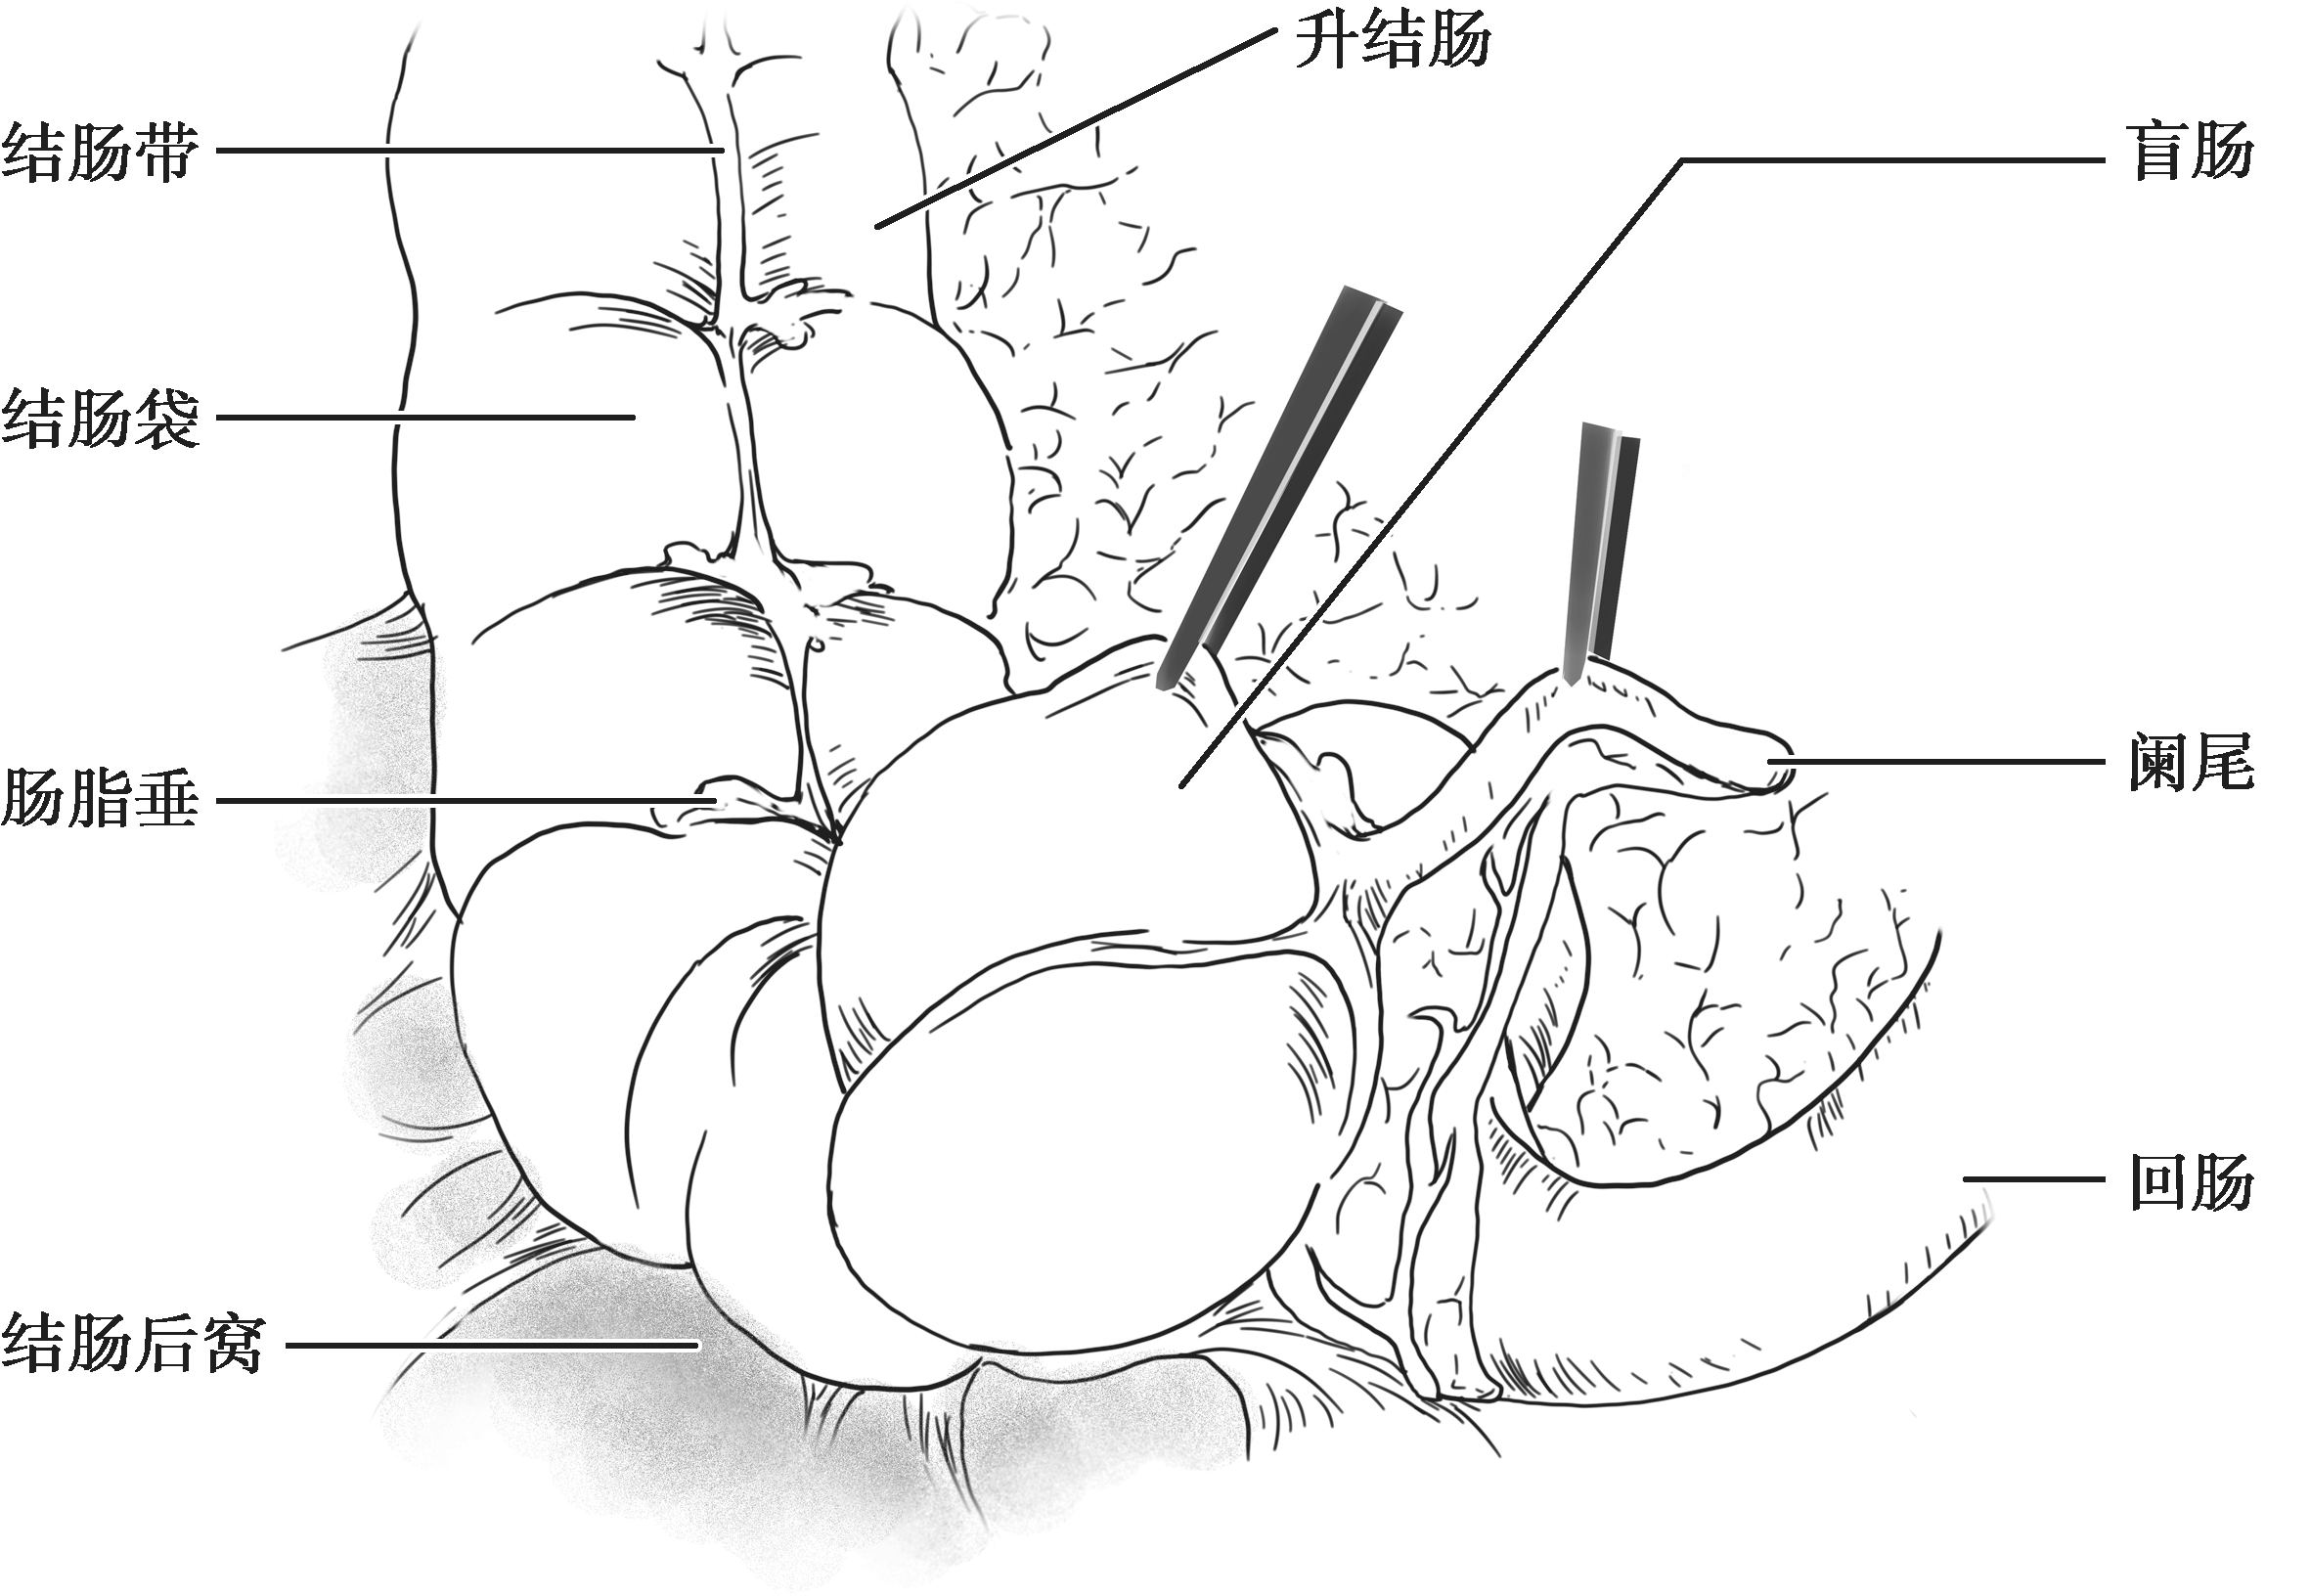

结肠是腹腔内围绕小肠袢的大容量管型结构,是大多数脊椎动物消化系统的重要组成部分,有其鲜明的解剖学特点,包括结肠带、结肠袋和肠脂垂。结肠带明显可见,由肠壁的外纵肌增厚而成,沿结肠纵轴平行排列,3条结肠带均汇聚于阑尾根部,远端在直肠乙状结肠交界处与直肠延续。结肠袋是结肠壁由横沟隔开并向外膨出的囊袋状突起,是由于结肠带比结肠短约1/6而使肠管皱缩而成。肠脂垂是结肠浆膜面沿结肠带两侧分布的脂肪附属物(图2-1)。

图2-1 结肠的特征(结肠带、结肠袋和肠脂垂)及回盲部

盲肠是大肠的起始部分,也是最为短粗的一部分,位于右下腹髂窝内,上方为升结肠。新生儿期盲肠长约1.5cm,宽略大于长;2~4岁时长宽平衡,7岁时接近成人,为3~7cm。回肠是小肠的最后部分,止于盲肠的中后部。阑尾开口于盲肠的内侧面,在回盲部下方约2cm。

盲肠为腹膜内位器官,移动性较好,没有系膜结构,腹膜折叠常将盲肠附着在髂窝外侧和内侧。这些褶皱形成一个小的陷凹,称为结肠后窝(图2-1)。回肠和盲肠的韧带维持末端回肠和盲肠之间的夹角,形成了回肠末端突入盲肠的类似上下唇样的结构,称回盲瓣(图2-2)。这些结构在调节小肠内容物进入结肠的速度和预防回肠末端的食糜回流发挥重要作用[结肠内压可达80mmHg(1mmHg=0.133kPa)]。因此,临床上不要轻易切除回盲部;在短肠综合征的病例中,是否具有回盲瓣,对该病的诊断和预后均有重要意义。